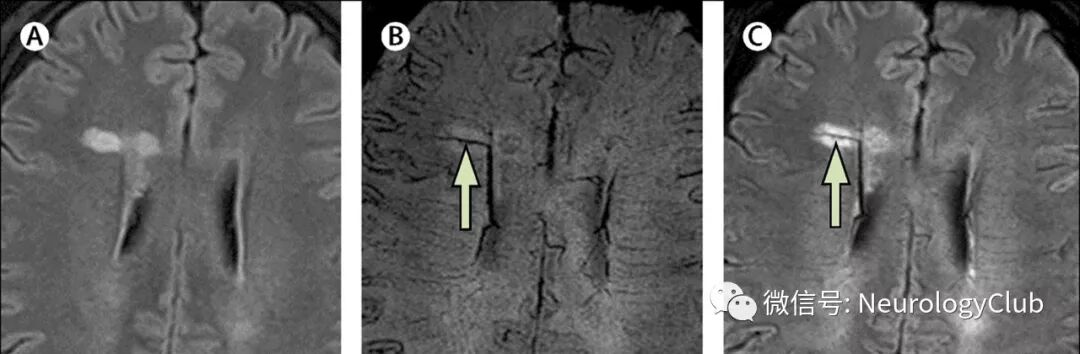

中央静脉征其具体表现为 T2WI、FLAIR上病灶中心呈低信号,此表现在脑室周围病灶 、脑深部白质病灶中容易发现。一般规定具有以下特点者判定为中央静脉征:(1)中央静脉直径小于2mm ;(2)无论形态如何,病灶静脉距离病灶边缘均几乎等距 ;(3)静脉部分和全部通过病灶 ,穿过病灶边缘不能超过两个部位 ;(4)病灶直径大于3mm ;(5)至少有两个不同方向的MRI病灶发现中央静脉 ;(6)不同方向的病灶中央静脉表现点状和细线 ,其中至少1个方向表现为细线状 。

图6:A:T2-FLAIR上可见累及脑室周围白质的典型卵圆形脱髓鞘病变;B-C:磁敏度加权成像和T2-FLAIR及磁敏度加权成像融合(T2-FLAIR *)可见中央静脉征